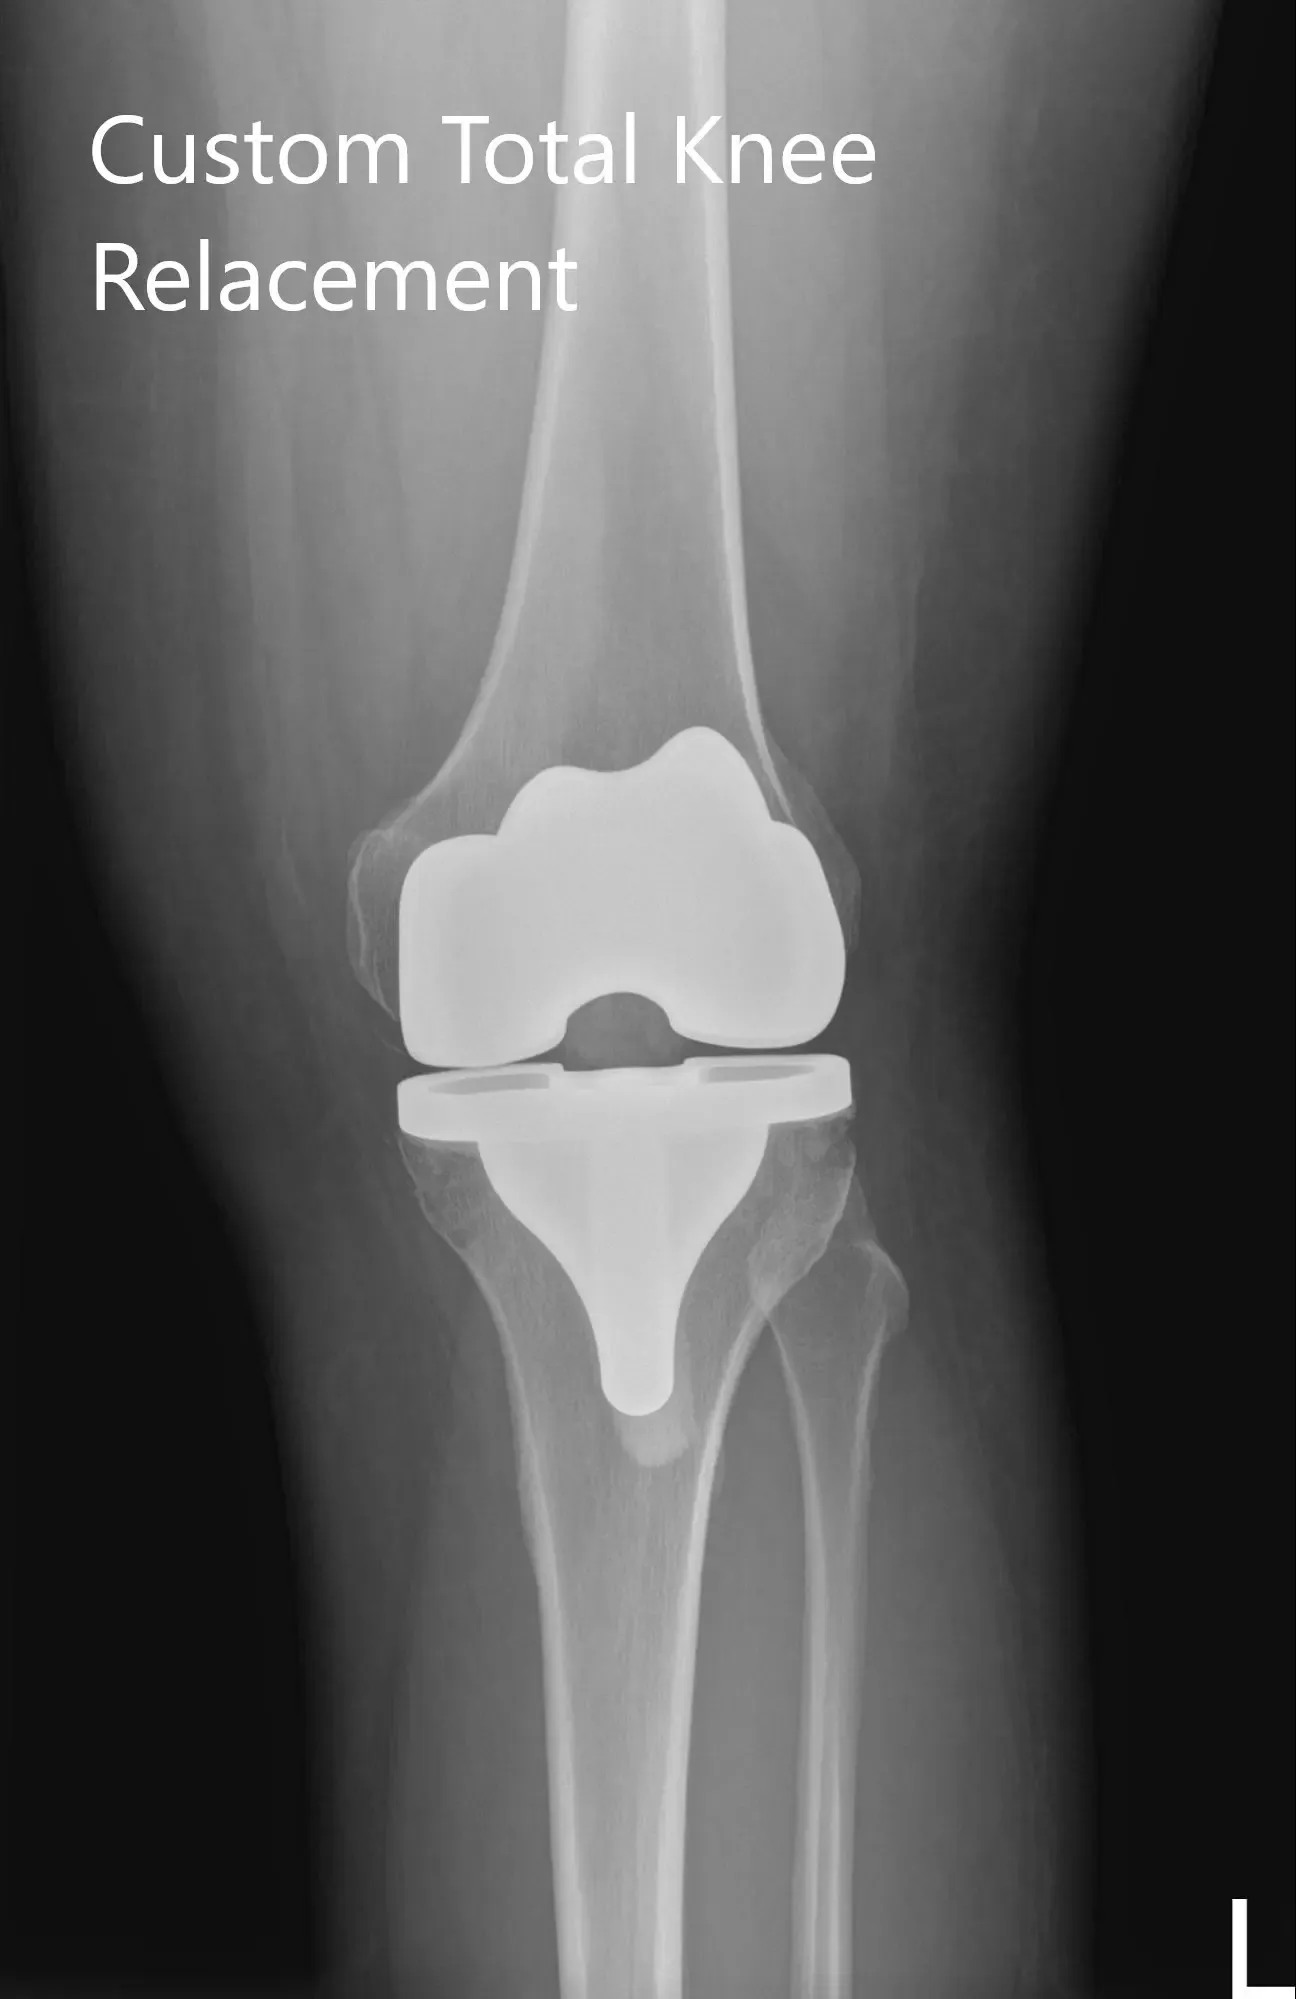

Radiografía postoperatoria de la rodilla izquierda que muestra imágenes AP y laterales

El paciente fue ambulatorio el mismo día de la cirugía. Informó de un buen control del dolor con medicación y un buen rango de movimiento alrededor de la rodilla izquierda. La herida del paciente estaba limpia, seca e intacta. Tenía una excelente adherencia a la fisioterapia y al programa de ejercicio en casa. No mostró dolor (0/10) y un excelente rango de movimiento tras 3 meses.

El paciente había terminado con éxito su fisioterapia y volvió a trabajar como profesor. Le encanta la libertad de movimiento jugando entre niños. Pudo volver a hacer senderismo moderado y montar en bicicleta sin dolor. La pareja se alegró diciendo que los resultados habían superado sus expectativas. Él responde cuando es necesario.